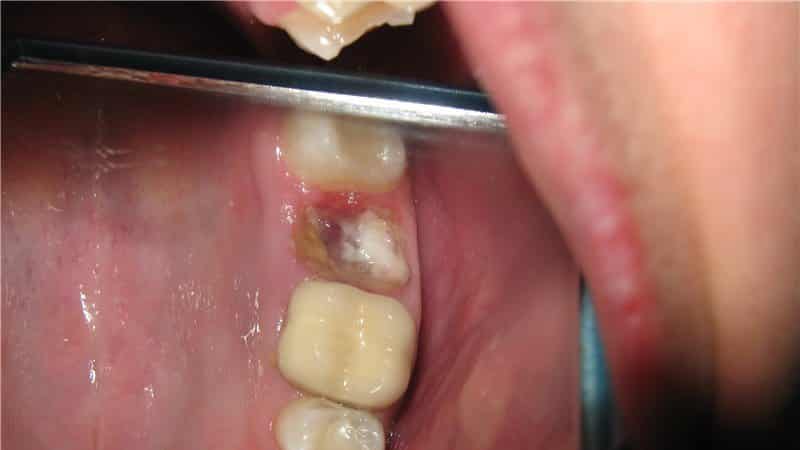

На поверхности лунки виден некроз тканей (почернение), образование белого налета, гнойные пробки и другие аномалии.

Изо рта идет характерный запах гниения и гноя.